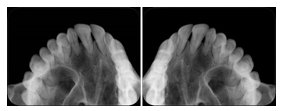

OO.1.2 Ophthalmology

1. A patient in rural Canada visits a general ophthalmologist and is found to have diabetic macular edema. The general ophthalmologist would like to discuss the case with a retina specialist before performing laser surgery. A fluorescein angiogram is done with multiple retinal images taken in a timed series after an intravenous injection. The images along with a Structured Display are shared via a Health Information Exchange with a retina specialist in Calgary, who opens them using his Ophthalmology EMR software and consults via phone with the general ophthalmologist. Both physicians view the images in the same layout so the retina specialist can provide accurate guidance for treating the patient.

2. A patient in rural Iowa visits his primary care physician for management of diabetes. Three non-mydriatic (patient's eyes are not dilated) photographs are taken of the back of each eye, and forwarded electronically along with a Structured Display to an ophthalmologist in Iowa City. The ophthalmologist reads the photos in an agreed upon layout so there is no mistake about what portion of which eye is being viewed. The ophthalmologist is able to tell the primary care physician that his patient does not need to come to Iowa City for face to face ophthalmologic care, but that there is a particular view of the left eye that should be photographed again in 6 months.

Ophthalmic Retinal Study Structured Display

Figure OO-3. Ophthalmic Retinal Study Structured Display